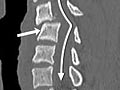

Computed Tomography (CT) Scan of the Spine

A CT scan uses X-rays to make detailed pictures of the spine and vertebrae.

CT scan of the spine

Normal:

- Spinal bones (vertebrae) are normal in shape, number, and alignment.

- The discs and joints that support the spine are normal.

- The spinal canal is normal in size and shape.

- If contrast material is used, it flows evenly through the spinal canal. No narrowing or blockage of the spinal canal is present.

- None of the nerves leaving the spinal cord are compressed or pinched. No growths or bulges are present.

Abnormal:

- Spinal bones (vertebrae) are missing, damaged, or out of alignment.

- One or more discs may be damaged. One or more herniated discs are found.

- The flow of contrast material through the spinal canal is restricted or blocked, which may mean narrowing of the canal (spinal stenosis).

- The vertebrae show signs of arthritis or bone problems caused by osteoporosis.

- A condition that has been present from birth (congenital) is present in the spine or the vertebrae.

- An abscess or spinal tumor is found.